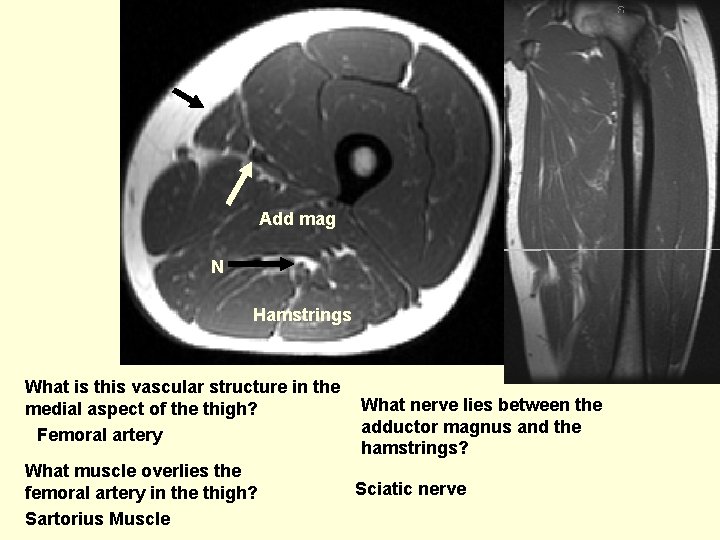

Add mag N Hamstrings What is this vascular structure in the medial aspect of the thigh? Femoral artery What muscle overlies the femoral artery in the thigh? Sartorius Muscle What nerve lies between the adductor magnus and the hamstrings? Sciatic nerve